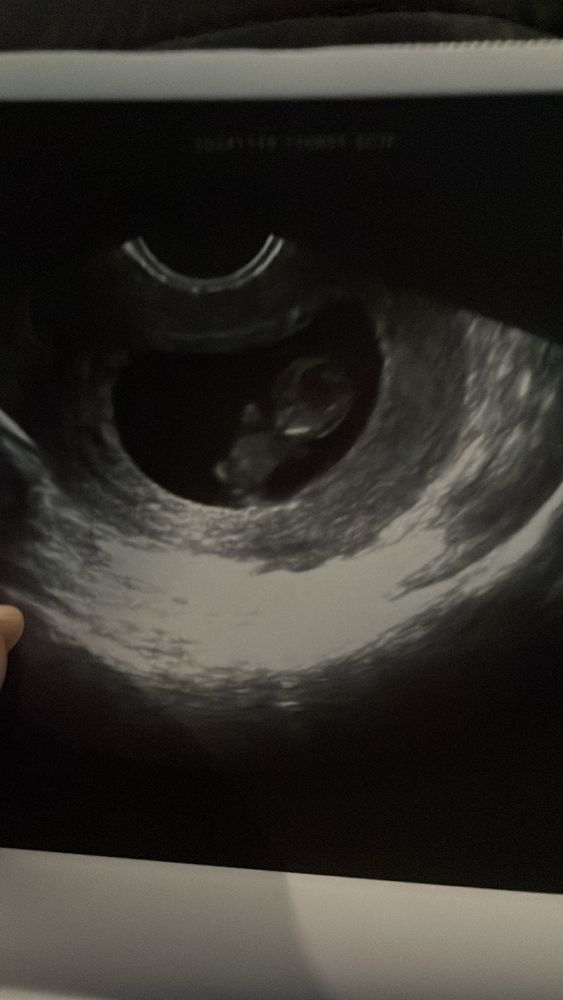

9 недель 4 дня)

Какой ты деловой лежишь там) ноги руки шевелятся, сердечко стучит) как это удивительно и странно - внутри меня живёт человек...)

Дали направление на первый скрининг и поставили гсд) ну не вписалась да по сахару чуток - 5,1) значит будем следить за питанием и трескать поменьше сладкого)